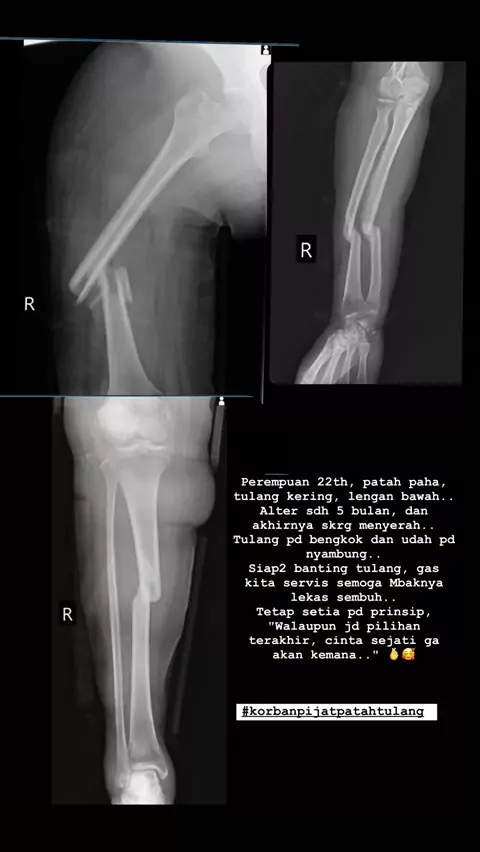

Walau jadi pilihan terakhir, cinta sejati ga akan kemana 🥰🫰 . .#ortopedibogor#doktertulangbogor#doktertulang#patahtulang#pijatpatahtulang#doktertulangjakarta##korbanpijatpatahtulang